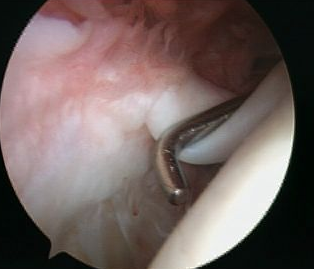

Arthroscopy

Normal insertion of superior labrum onto glenoid

Snyder Arthroscopic Classification SLAP tears